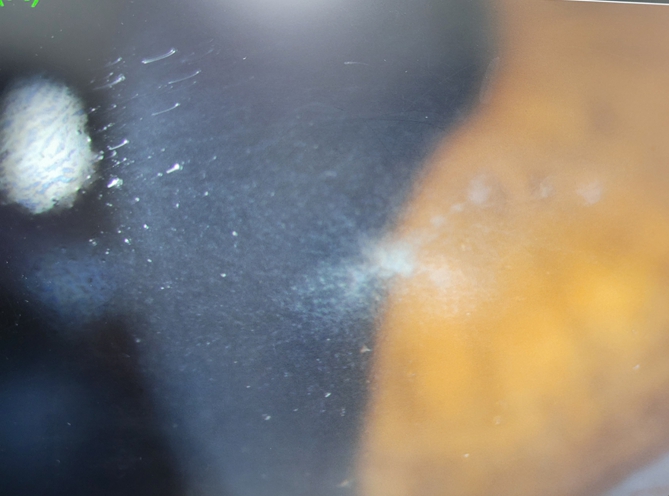

楊姓病患左眼中、下半部,長出橫向且呈現類似樹幹的角膜病變。圖/達特楊眼科聯盟執行長洪啟庭醫學博士提供

洪啟庭表示一名患者,35歲的楊姓男子上門就醫左眼視力僅剩下0.2,而且角膜呈現彎彎曲曲的病變,細看之下很像樹幹型狀。另外螢光染色澤見到明顯的角膜缺陷,而且測試角膜敏感度也大幅降低,幸好發炎反應只在角膜,尚未侵犯眼睛後方造成角膜蓄膿;另外在眼皮周遭與鼻尖,並泡疹水泡出現。再詢問個案:楊姓年輕人是一般的服務業,白天必須常接觸電腦與智慧型手機。晚上約十點關燈就寢,但一時又睡不著,於是開始滑手機,沒想到越滑越起來勁,甚至滑到凌晨三點;若隔天沒上班,甚至整夜未眠。病患表示多年前,他曾經在頭皮部分長過帶狀泡疹,但是當初沒有侵犯眼睛。

楊姓病患治療一星期後,角膜樹幹末端慢慢收縮、角膜上皮逐漸收口,疼痛、異物感與流淚也大幅減少。圖/達特楊眼科聯盟執行長洪啟庭醫學博士提供

經過檢查與評估後,洪啟庭以「泡疹病毒角膜炎」為主要診斷,建議治療期間一定不要玩手機,並立即施予抗泡疹病毒的藥膏與人工淚液,治療與保護角膜細胞。另外也點眼用抗生素,預防來自細菌或黴菌的二次感染。在治療一星期後,病患的病灶稍微改善,樹幹末端也慢慢收縮、角膜上皮也逐漸收口。而且病人的疼痛、酸澀、異物感與流淚等症狀、也大幅減少,病人舒服許多,目前仍在持續治療中 。